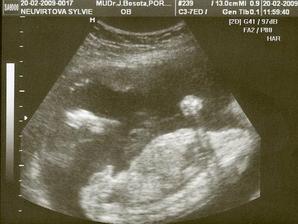

20.2.Byli jsme na dalším uTZ u jiného pana Doktora, který nám jasně ukázal, že čekáme chlapečka🙂)))teď jsem z toho fakt dost zmatená,ale věřím chlapečkovi...)

10.2.poslední genetický UTZ v Olomouci, kde nám potvrdili, že miminko je zdravé..Podle pana primáře čekáme tentokrát holčičku..